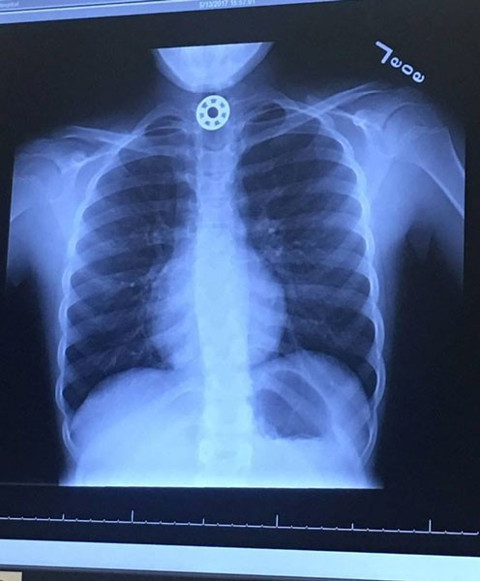

Stres çarkı bir çocuğun hayatını elinden alıyordu!

Galerinin tamamı için tıklayınızSTRES ÇARKINA DİKKAT Ebeveynler için bazı tavsiyelerde bulunan anne: "Stress çarklarının hiçbirinde yaşa uygun uyarılar verilmiyor. Bu nedenle bunların boğulma tehlikesi doğurduğu aklınızdan çıkmasın."